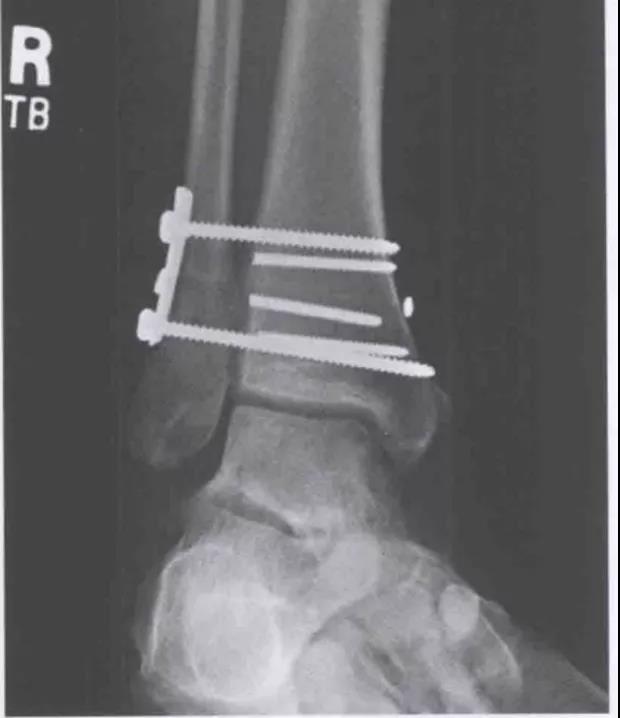

术后DR

术前DR